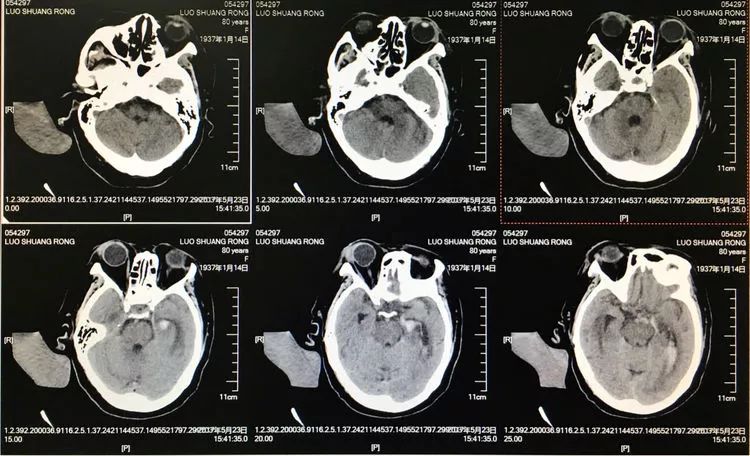

患者女性,80岁,以SAH于2017.5.20急诊入院,CTA示基底动脉顶端动脉瘤。

2.17.5.27 DSA+栓塞

左椎动脉正位造影可以看到指向左方的子瘤。